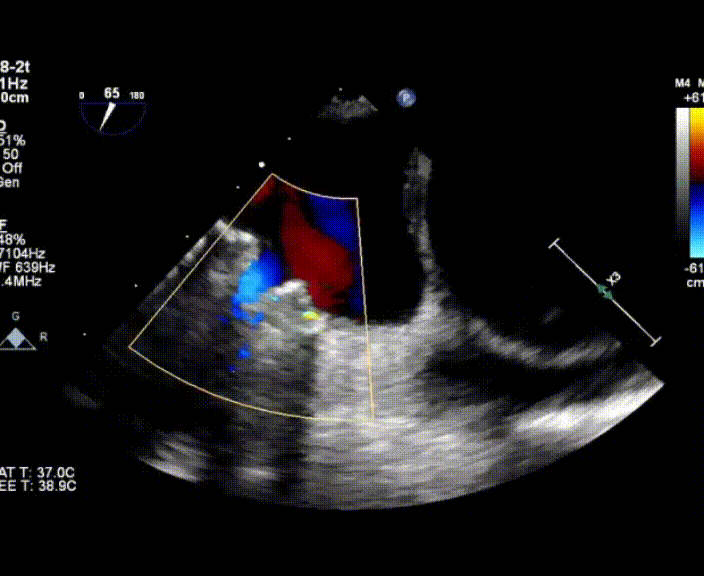

超聲心動圖提示:右心增大,右室肥厚,左室測值偏小,房間隔中份探及修補術后回聲,房水平未見殘余分流,三尖瓣重度反流,重度肺動脈高壓,中度肺動脈瓣反流,左室收縮功能測值正常,右室收縮功能減低 。

術中首先在局麻下穿刺股動脈、股靜脈,完成心導管檢查評估后轉為全麻,在食道超聲引導下穿刺房間隔,穿刺成功后將加硬導絲送入左上肺靜脈建立軌道,根據(jù)患者病情行球囊預擴張后植入6mm孔徑房間隔造孔支架,經(jīng)透視及食道超聲評估支架左右盤展開良好,夾持于房間隔兩側,固定穩(wěn)定、位置良好,食道彩超顯示房水平右向左為主分流,分流孔直徑符合預期大小,心導管檢查評估達到預期效果,釋放造孔支架。術后12h患者下床活動,恢復順利,擬于近日完善術后評估后出院。